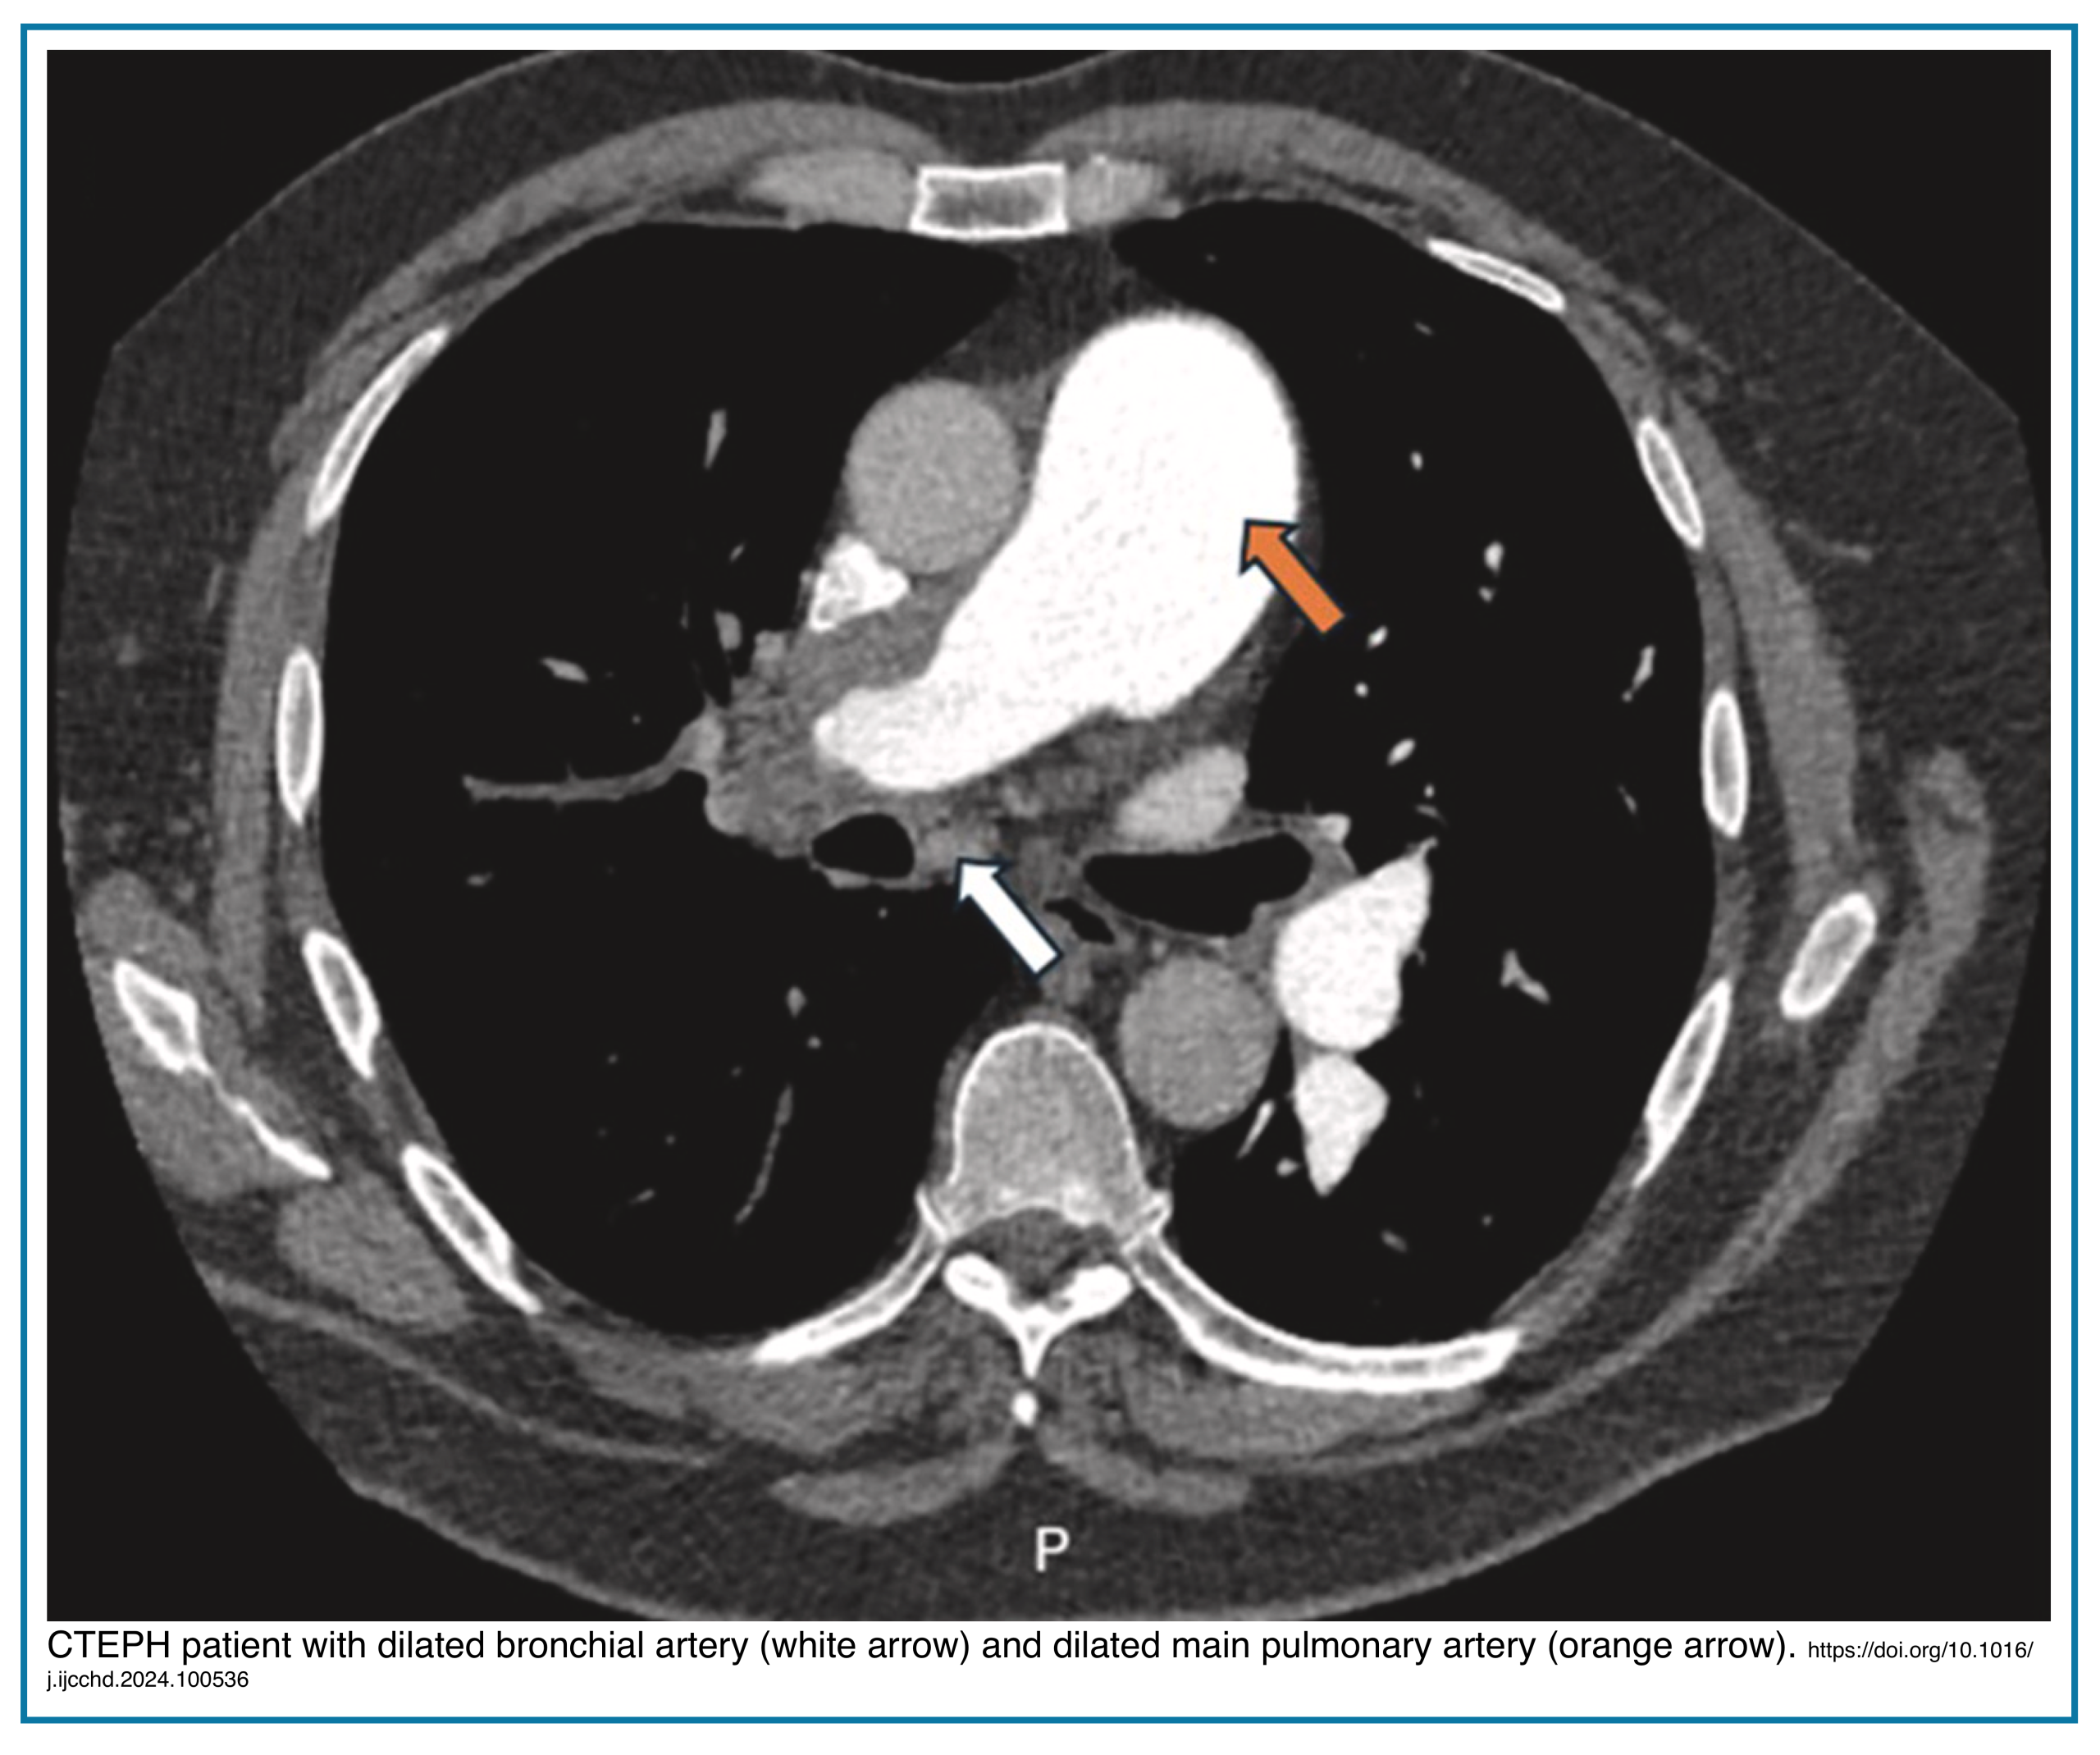

Enlarged Bronchial Arteries

Markedly enlarged bronchial arteries (>1.5 mm diameter in the mediastinum) are one of the most specific signs of chronic disease, indicating long-term compensation (Figures below).

C. Systemic Collateral Circulation

- Markedly Enlarged Bronchial Arteries (explained above).

| Systemic Collateral Circulation | Absent. | Markedly enlarged bronchial arteries (>1.5-2mm) – a highly specific sign. |